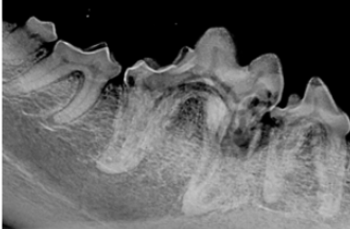

On this episode of The Vet Blast Podcast, veterinary dentist Jan Bellows talks with Dr. Adam Christman about the different classifications of tooth resorption, plus offers various treatment approaches.

Understanding how tooth resorption is diagnosed and classified enables you to provide better patient care and to increase patient comfort.